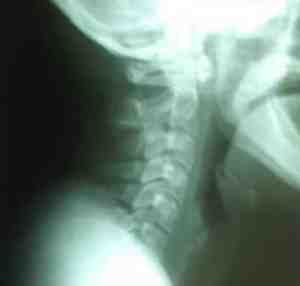

Hernia discal cervical. Imágenes y breve revisión

Hernia discal cervical. Imágenes y breve revisión.

Resumen:

La hernia discal cervical no es más que

es la salida del núcleo pulposo a través del anillo fibroso, debido a

una lesión del disco intervertebral, dando generalmente como resultado,

un cuadro clínico neurológico por compresión de las raíces nerviosas del

segmento vertebral afectado. La clínica unida a la radiología simple,

constituye el pilar fundamental en el diagnóstico de la hernia discal

cervical.